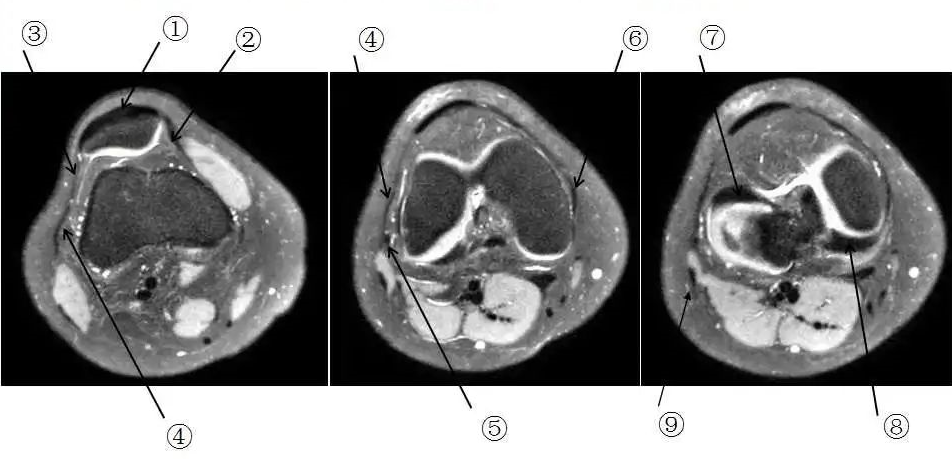

我们先一起来学习一下解剖

那么我们刚刚看到信号增高的就是髂胫束,排除了半月板和外侧副韧带的问题,那么膝关节外侧疼痛是不是这个原因导致的呢?